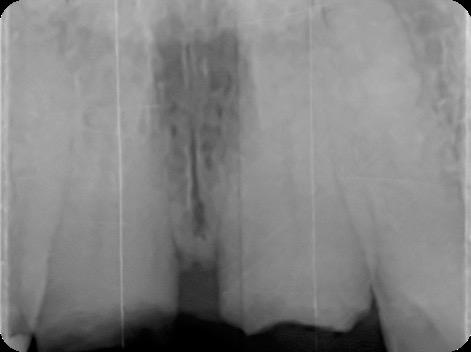

Fig 2. Intraoral radiograph indicating tooth structural loss extent.

Fig 4. Alveolar bone imaging. The alveolar bone was intact, and the alveolar crest was approximately 4mm apical to the restorative margin.

Fig 9. Periapical radiograph for verification of proper seating of the scanbodies.

Fig 13. Radiograph of implants, grafts and Provisionals.